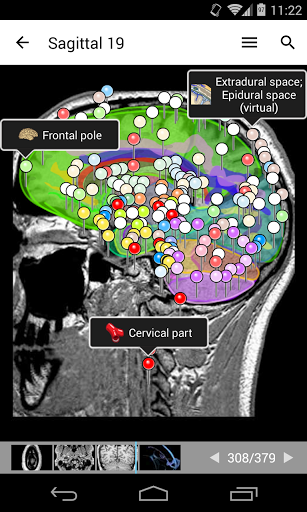

e-Anatomy tiene más de 26 000 imágenes que contienen series de imágenes en vistas axiales, coronales y sagitales, así como radiografías, angiografías, imágenes de disección, gráficos anatómicos e ilustraciones. Todas las imágenes médicas fueron etiquetadas cuidadosamente, más de 967 000 etiquetas disponibles en 12 idiomas, incluida la Terminologia Anatomica latina.

- Desplácese por los conjuntos de imágenes arrastrando el dedo

- Acerque y aleje el zoom

- Toque las etiquetas para mostrar las estructuras anatómicas

- Seleccione las etiquetas anatómicas por categoría